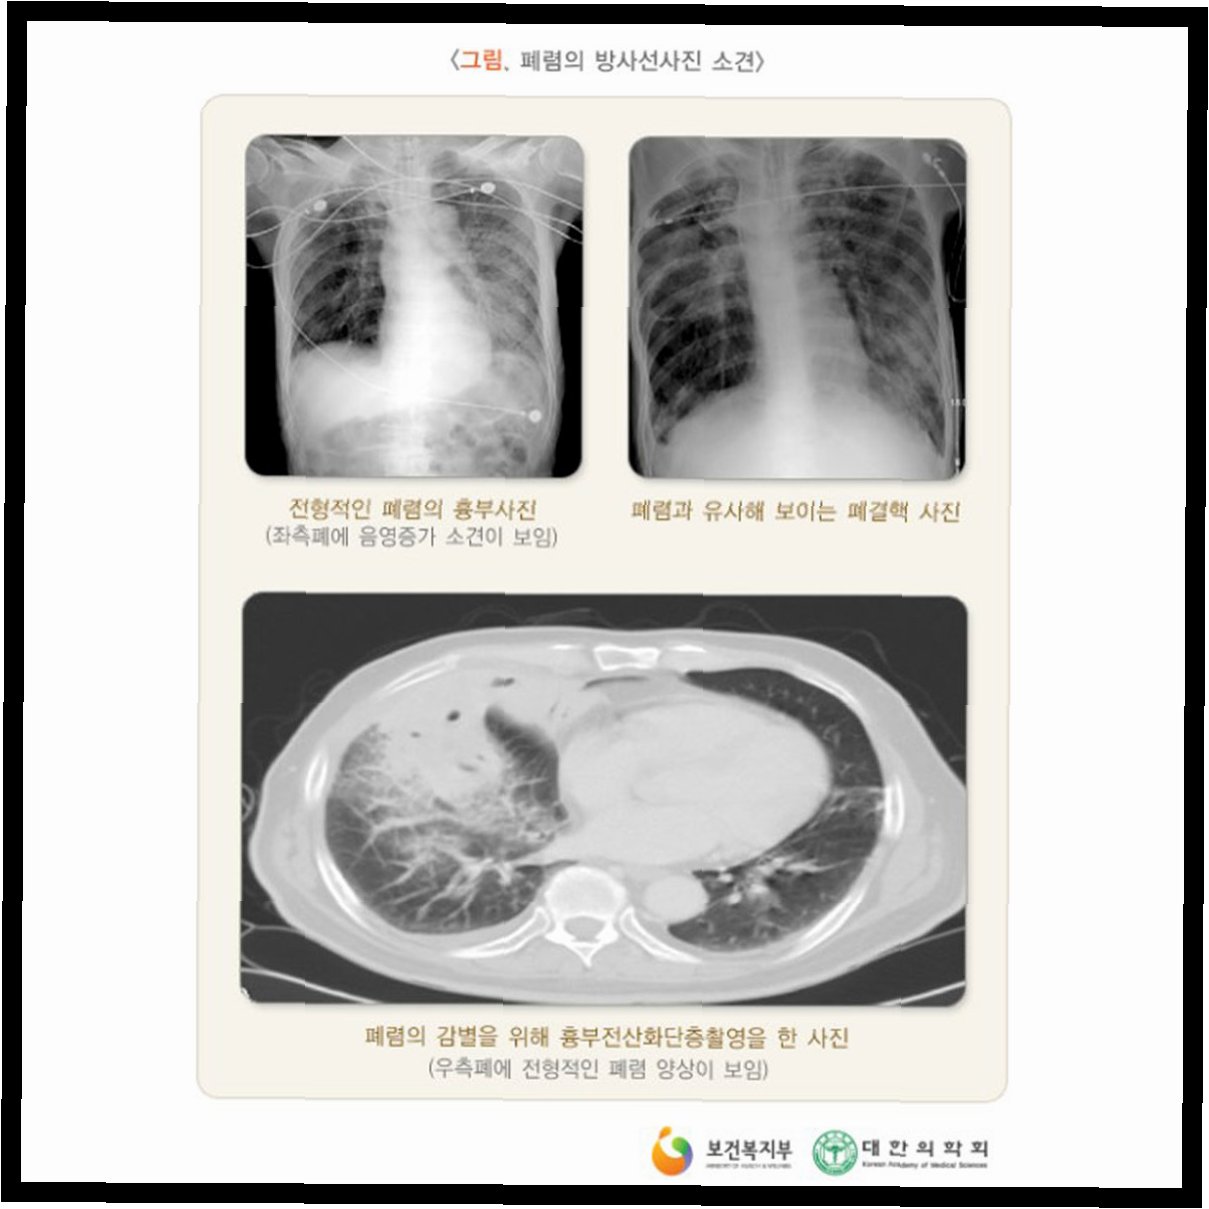

국가건강검진, 흉부 엑스레이 검사 대상 축소의 배경그동안 국가건강검진에서 일률적으로 시행되던 '흉부 방사선(엑스레이) 검사' 대상이 앞으로는 발병률이 높은 50세 이상으로 축소된다. 보건복지부는 '2025년 제3차 국가건강검진위원회'를 열고 이같은 내용을 담은 '국가건강검진 흉부 방사선 검사 개선방안'을 심의·의결했다. 흉부 엑스레이 검사 축소의 주요 원인: 비용 대비 효과성그간 흉부 방사선 검사는 주로 폐결핵 발견을 목적으로 시행돼 왔으나, 실제 폐결핵 유병률은 0.04% 수준에 머물러 왔다. 복지부에 따르면 2023년 기준 흉부 방사선 검사를 통한 폐결핵 발견율은 0.03%에 불과한 반면, 검진 비용은 연간 1426억원이 소요됐다. 이는 전체 국가건강검진 비용의 약 21%에 달하는 수치다. ..